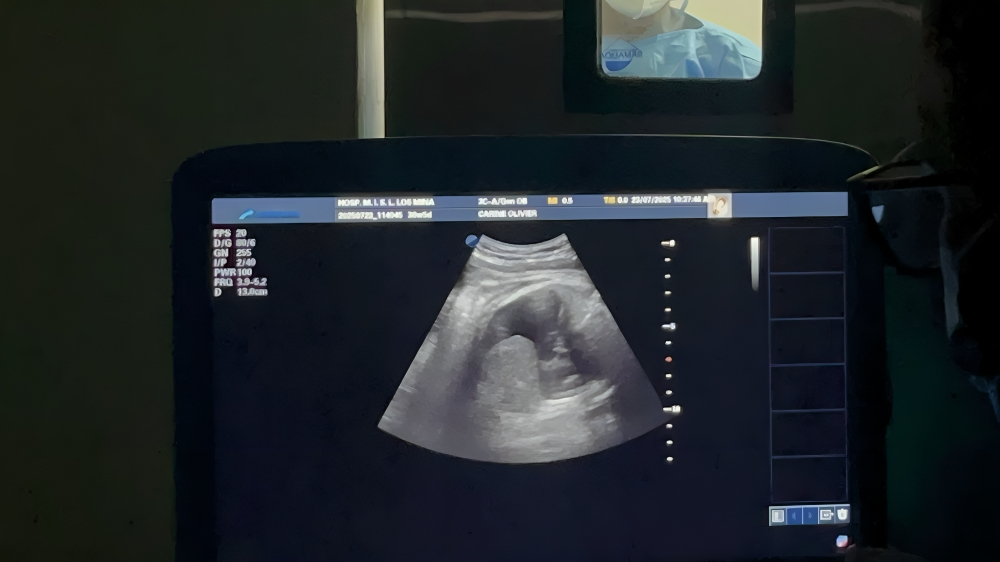

- Intervención prenatal coordinada por los doctores Ramiro Díaz y Virginia Pérez, quienes realizaron un drenaje toracoamniótico para extraer líquido acumulado en las cavidades pleural y pericárdica del feto, condición que hubiera comprometido su capacidad respiratoria al nacer.